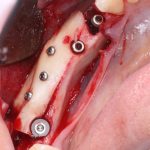

Изоляция области аутографта и имплантатов барьерной мембраной.

Конкретно в этом клиническом случае между костным аутотрансплантатом, ложем и имплантатами есть пустое пространство. Если его не изолировать от мягких тканей, они прорастут и осложнят интеграцию аутографта. Поэтому я решил перекрыть костный блок барьерной мембраной, пусть это делает хирургическую операцию немного дороже.

— я использовал барьерную мембрану Geistlich Bio-Gide, которая имеет две разные поверхности: с одной стороны она рыхлая «адгезивная», с другой — гладкая и прочная. Как укладывать — на результат не влияет, но в плане удобства рыхлую поверхность мы «приклеиваем» к тому, на чем требуется барьерную мембрану удержать. В данном случае хотелось бы удержать её на костной поверхности — следовательно, мы укладываем её рыхлой поверхностью к кости.

— ты знаешь, что барьерная мембрана может выполнять две функции, каркасную и изолирующую. Первая функция требует обязательной фиксации и натяжения, вторая — нет. В нашем случае «каркасом» регенерата является костный блок, а барьерная мембрана нужна только для изоляции. Поэтому она не требует натяжения и фиксации пинами.

После я внимательно проверил, что костный блок и имплантаты полностью перекрыты. Теперь рану можно ушивать.